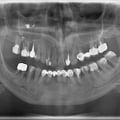

Імплантація 16,17,18 без врахування жодних правил оклюзії та знань в імплантології